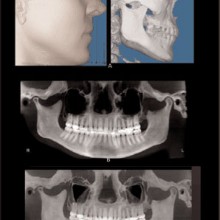

MAXIMUM INTENSITY PROJECTION (MIP) can be used to highlight features. The anatomic features associated with the brightest pixel or voxel intensity are projected on the display screen. This method creates a high-contrast image, but the brighter pixels/voxels may mask or superimpose over less-bright pixels, thus potentially hiding important anatomic features. MIP projections of a CBCT volume or slab (right or left sides) may be a useful method to produce constructed panoramic and cephalometric images for orthodontic purposes (Figure 3). Shaded surface Rendering (SSR) is useful for high-contrast imaging such as bone. SSR techniques allow the operator to set a pixel or voxel intensity threshold that excludes structures lower than the selected threshold, and renders all structures greater than the selected threshold (Figure 3). SSR creates a three-dimensional model that can be rotated as an object to be viewed from any angle. When the tissue contrast is not high, then the selected threshold may not perfectly render the desired anatomy. Volume rendering (VR) also creates a three-dimensional model using no

ORTHODONTIC RECORDS: The greatest recent innovation has been the inclusion of the spatially true-size three-dimensional digital image data into the orthodontic records. Ultimately the three-dimensional records will replace the two-dimensional records. The current generation cone beam CT promises to produce, in a single scan, enough information to eliminate the need for conventional panoramic, occlusal, cephalometric, selected periapical, and tempormandibular-joint tomographic studies and possibly plaster dental models. The CBCT data will be superior to that gained from the compiled series of two-dimensional images, and the absorbed dose will be less.

With the traditional two-dimensional dental-imaging series some areas of anatomy are poorly visualized. These three-dimensional scans can give valuable information about other areas of the dentition such as the position of the upper incisor roots relative to the lingual cortical border of the palate to plan retraction, the amount of bone available in the posterior maxilla available for distalization, the amount of bone lateral to the maxillary buccal segments available for dental rather than skeletal expansion, airway information on the pharynx and nasal passages, upper root proximity to the maxillary sinus, the three-dimensional extent of an atrophied alveolar ridge, or the position of the lower incisor roots in bone. These scans also allow three-dimensional visualization of bony defects and supernumerary teeth in patients with cleft lip and/or palate. Additionally, axially corrected tomograms of the temporomandibular joints can be obtained from the same scan. The ability to visualize an axially corrected view of the temporomandibular joints with the teeth in occlusion on the same reconstructed section is one significant advantage of the volume scan. Therefore, there is substantial “value-added” imaging benefits to these scans for complicated orthodontic patients.